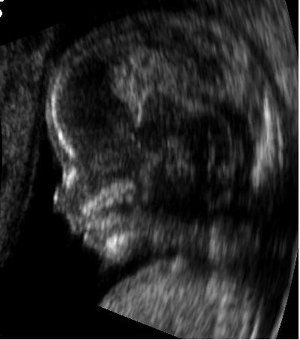

Ultrasound image of a foetus at 14 weeks. Public domain